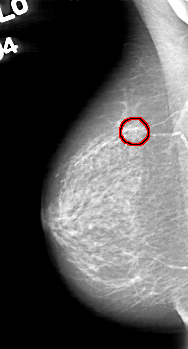

D_4044_1.RIGHT_MLO

FILE: D_4044_1.RIGHT_MLO.OVERLAY

TOTAL_ABNORMALITIES 1

ABNORMALITY 1

LESION_TYPE CALCIFICATION TYPE COARSE DISTRIBUTION CLUSTERED

ASSESSMENT 0

SUBTLETY 5

PATHOLOGY BENIGN

TOTAL_OUTLINES 1

BOUNDARY